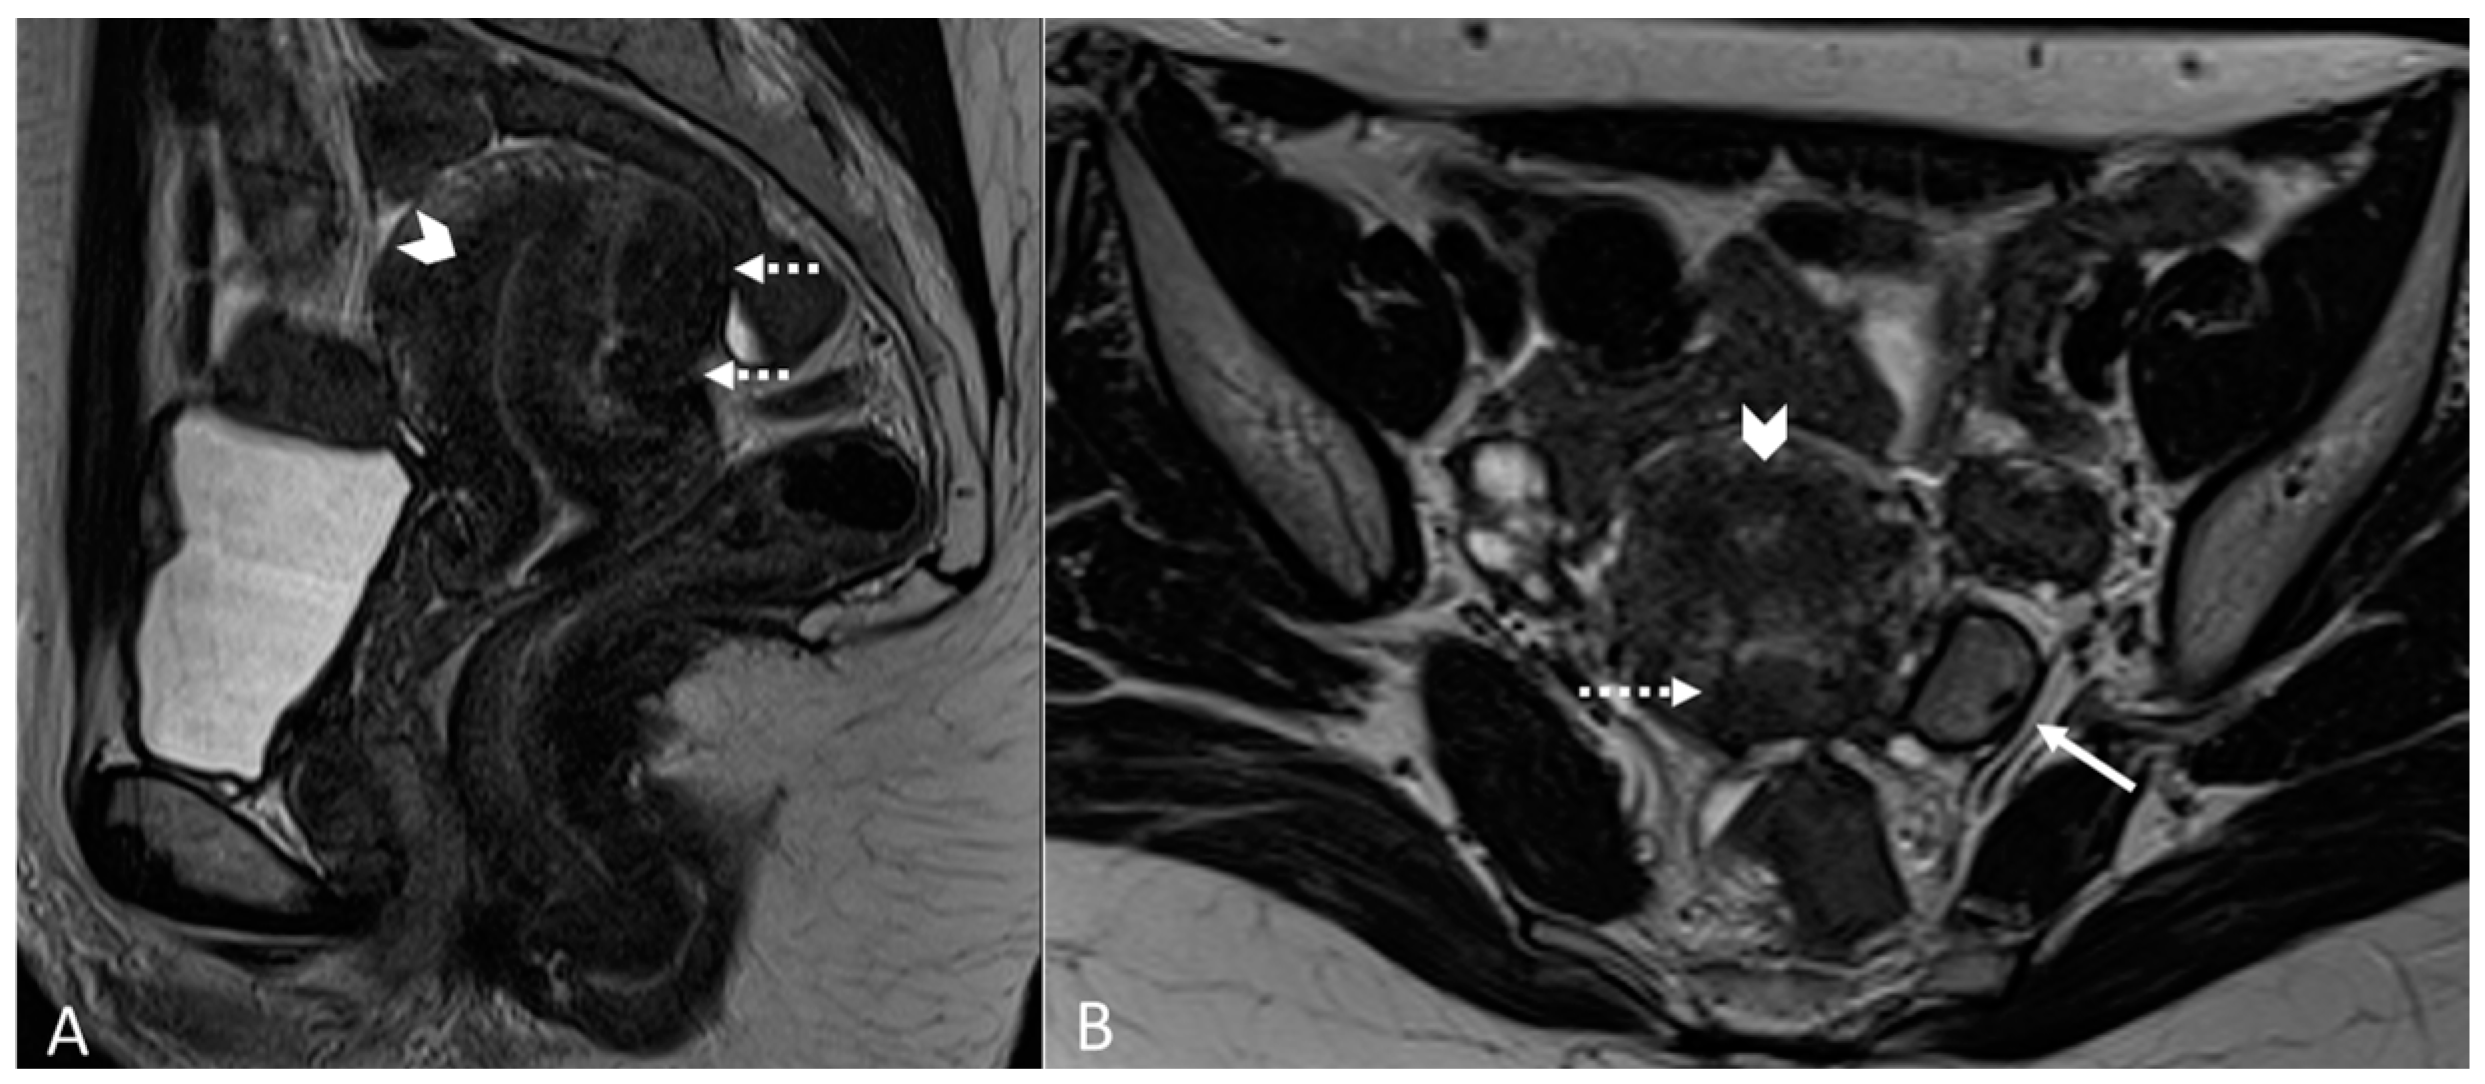

Generally, they appear hyperintense on fat-suppressed T1WI and T1WI (Figure 7 and Figure 8). The hyperintensity on fat-suppressed T1WI helps differentiate endometriomas from dermoid cyst and teratoma, which usually contain fat [51]. On T2WI, a variable signal can be obtained: a hypointense signal can affect variable portions of the cyst, sometimes also presenting a stratification, until a complete loss of the signal. This is called the shading sign and is correlated to the different state of hemoglobin degradation [52] (Figure 8). The T2 dark spot sign refers to hypointense spots in the wall of the cyst due to the presence of macrophages (Figure 9).

Figure 7.

Ovarian endometrioma in a 37-year-old female. (A) Axial T1WI; (B) Axial fat-suppressed T1WI. Typical aspect of an ovarian endometrioma (white arrows).

Figure 8.

Right tubo-ovarian endometriosis in a 25-year-old female patient with reported localized abdominal pain in the right iliac fossa, which increases intensity during the menstrual cycle. (A) Axial T2WI; (B) Axial fat-suppressed T1WI. Enlarged right adnexal cyst with incomplete septa denoting dilated tube (white arrows). The cystic content shows low signal intensity on T2WI and high signal intensity on fat-suppressed T1WI, consistent with hemorrhagic fluid.

Figure 9.

Diffuse internal and external adenomyosis in a 37-year-old female. (A) Sagittal T2WI; (B) Axial T2WI. Diffuse internal adenomyosis as demonstrated by diffuse hypertrophy of the JZ (white arrowhead in (A,B)), subserosal hypointense ill-defined mass in the posterior myometrium consistent with external adenomyosis (white dotted arrows in (A,B)), with associated deep endometriosis of posterior compartment. Left endometrioma with T2 dark spot sign (white arrow in (B)).